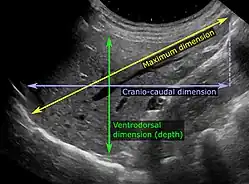

On abdominal ultrasonography, the liver can be measured by the maximum dimension on a sagittal plane view through the midclavicular line, which is normally up to 18 cm in adults.[2] It is also possible to measure the cranio-caudal dimension, which is normally up to 15 cm in adults.[2] This can be measured together with the ventro-dorsal dimension (or depth), which is normally up to 13 cm.[2] Also, the caudate lobe is enlarged in many diseases. In the axial plane, the caudate lobe should normally have a cross-section of less than 0.55 of the rest of the liver.[2]

Other ultrasound studies have suggested hepatomegaly as being defined as a longitudinal axis > 15.5 cm at the hepatic midline, or > 16.0 cm at the midclavicular line.[17][18]